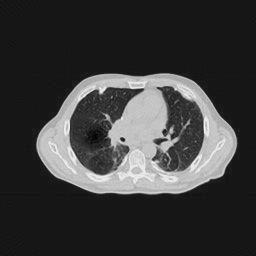

IV-C Few-View CT Reconstruction

In this section, the reconstruction performance of our proposed framework under few-view conditions will be tested. For the parallel and fan beam geometry, the number of views increases from to , uniformly distributing from to and to respectively. Such settings provide a complete benchmark of reconstruction performance, ranging from extremely sparse to relatively complete, full-view CT reconstruction. The experiment results are shown in Fig.5. Additionally, the ground truth, few-view ( views), and full-view ( views) CT reconstruction results of different methods are shown in the first and third rows of Fig.7 (parallel-beam, LIDC-IDRI dataset), and Fig.8 (fan-beam, LIDC-IDRI dataset).

IV-D Limited-Angle CT Reconstruction

To test the proposed framework’s performance on limited-angle reconstruction, we redo the experiment in the above section with the angular range changing from to for parallel-beam geometry and to for fan-beam geometry, one projection per degree. The experiment results are shown in Fig.6. Also, the ground truth and the limited-angle CT reconstruction results of different methods are shown in the row of Fig.7 (parallel-beam, LIDC-IDRI dataset), and Fig.8 (fan-beam, LIDC-IDRI dataset).

SNR/SSIM

16.31dB/0.55

20.83dB/0.83

13.37dB/0.61

16.65dB/0.79

13.40dB/0.73

16.85dB/0.65

22.47dB/0.78

14.25dB/0.63

22.99dB/0.62

19.51dB/0.56

(a) Ground Truth

30.15dB/0.85

(b) ASD-POCS

39.35dB/0.94

(c) RBP-DIP

27.10dB/0.78

(d) DIP

23.88dB/0.65

(e) MED50

20.59dB/0.60

(f) RED-CNN

Conventional IR methods, even those with the help of regularizations such as total variation, are prone to artifacts when constrained by few-view and limited-angle conditions. However, as illustrated in the first and second rows of Fig.7b, and Fig.8b, these images still contain meaningful information which can be used to guide DIP related reconstruction methods, despite the presence of artifacts.

DIP related methods, which leverage the hierarchical structure of neural networks as a powerful prior, can better handle the aforementioned challenge. However, the original DIP method has its own limitations. It cannot generate detailed images or effectively enhance its accuracy as the number of measurements increases. For instance, in Fig.5a, the ASD-POCS algorithm achieves an approximate SNR gain of dB when the number of views increases from to , while the DIP method only attains an approximate dB gain. This problem is also shown in the last row of Fig.7, and Fig.8. Moreover, the DIP method may produce neural network specific artifacts, as shown in Fig.7d, Fig.8d, and Fig.12c. These artifacts are particularly problematic as they are often considered more undesirable than streak artifacts. Radiologists, with their professional experience, can interpret and account for streak artifacts, whereas network specific artifacts may prove more challenging to identify and address.

The proposed RBP-DIP framework combines the two approaches utilizing the newly devised RBP connection so that inherits the benefits of both methods. In Fig.4, the RBP-DIP method’s attainment of a 5dB SNR enhancement over the ASD-POCS method, despite exhibiting a larger loss. This implies that the improvement is not caused by the further minimization of the loss function but by the ability to choose a more reasonable reconstruction result from all candidates with similar losses. This is precisely the direct evidence of the successful combination of conventional IR and deep image prior in the proposed RBP-DIP framework. Subsequently, the improvement surpassing the original DIP method indicates the efficacy of the RBP connection. Moreover, by employing the RBP connection, neural network specific artifacts can be rectified effectively. As a result, substantial advancements can be shown in Fig.5, Fig.6, Fig.7, and Fig.8.

Also, Fig.5 and Fig.6, particularly Fig.6b, show that an increasing number of views does not sufficiently lead to improved performance of pre-trained models. The reason is that pre-trained models aim to learn the mapping between the input and the corresponding output from training datasets, rather than actually solve the corresponding inverse problem. Increasing the number of views cannot directly strengthen this mapping. Conversely, the proposed RBP-DIP directly minimizes the inconsistency between the ground truth and reconstructed images under the same measurements. Increasing the number of views reduces the dimensions of the solution space and thus benefits both network optimization and the iterative reconstruction (IR) algorithms integrated in the RBP connection. This outcome is further verified in the last row of Fig.7, and Fig.8, where RBP-DIP considerably outperforms other methods.